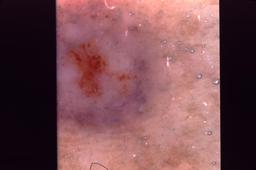

{

"age_approx": 40,

"anatom_site_general": "lower extremity",

"concomitant_biopsy": true,

"dermoscopic_type": "contact non-polarized",

"diagnosis_1": "Benign",

"diagnosis_2": "Collision - Only benign proliferations",

"diagnosis_confirm_type": "histopathology",

"image_type": "dermoscopic",

"lesion_id": "IL_8263283",

"patient_id": "IP_8318198",

"sex": "male"